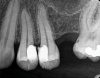

(3.) Preoperative radiograph of asymptomatic carious exposures on teeth Nos. 12 and 13.

Figure 3

(4.) Postoperative radiograph of teeth Nos. 12 and 13 following treatment with direct pulp caps using a bioceramic dentin substitute material.

Figure 4

The goal of direct pulp capping is to cover healthy or reversibly inflamed pulps that have been mechanically exposed during operative procedures or trauma.3 In direct pulp capping procedures, the chosen material is applied directly to the pulp in an effort to maintain pulp vitality and encourage the formation of directly adjacent tertiary reparative dentin (Figure 3 and Figure 4).7 Clinical studies have shown a greater rate of success when direct pulp capping is performed using MTA (85%) when compared with calcium hydroxide (52%) and similar rates of success when MTA is compared with newer calcium silicate materials.5,11 Histologic studies have shown an increase in dentin bridge formation and lower levels of pulpal inflammation adjacent to bioceramic direct pulp caps, including those placed with MTA and those placed with newer bioceramic materials.3,12